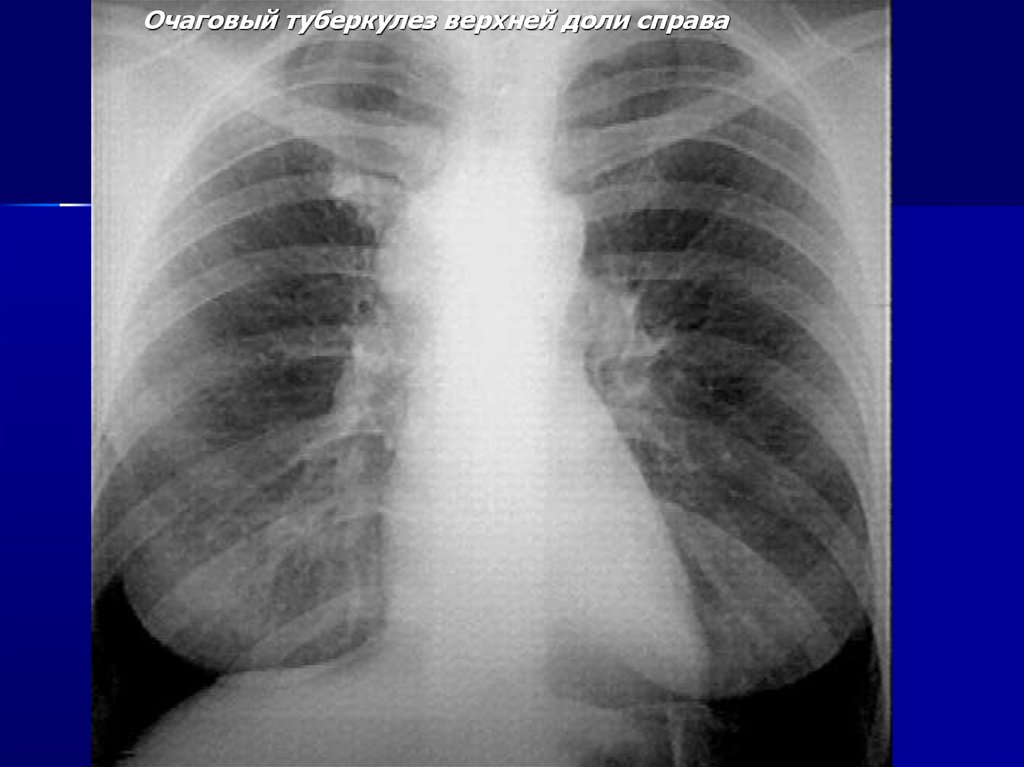

Очаговый туберкулез верхней доли справа